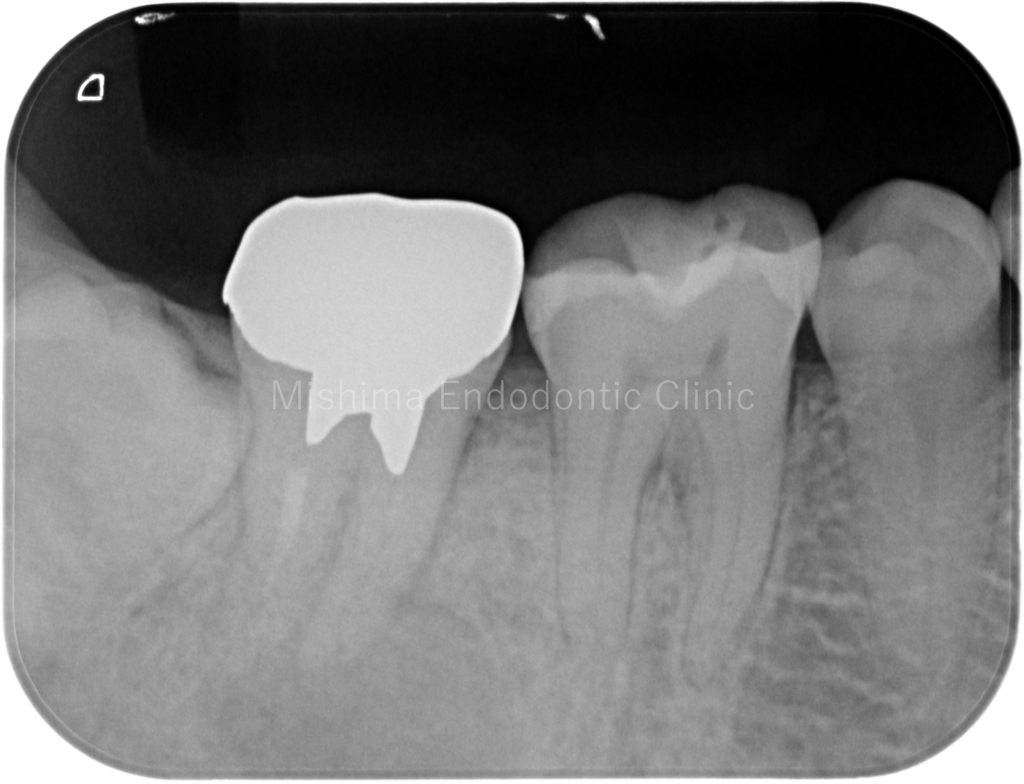

After

術直後